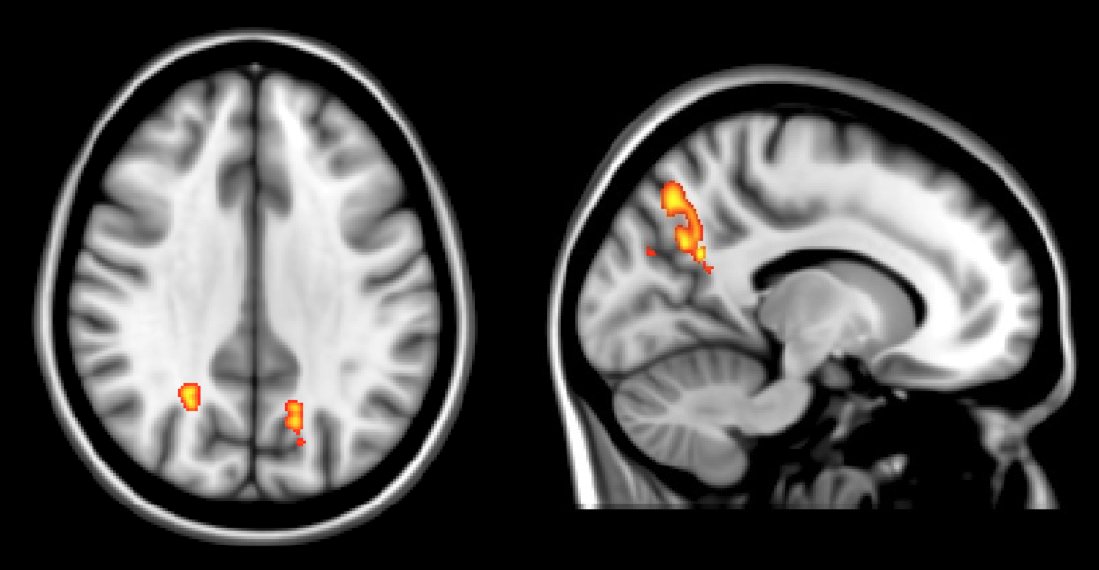

Is the wakefulness-promoting, consciousness-enabling influence of the brainstem left-lateralized in humans?

Seems unlikely, right? In 2016 we did a lesion study of coma and our results suggested a left lateralization to a dorsolateral pontine tegmentum arousal-promoting region.

This was a small enough sample I think we all assumed the apparent laterality could have been by chance.

Ever since this paper Joel Geerling (@geerling_lab) and I have been collecting brainstem lesion cases @uiowaneuro in search of counter evidence that would challenge this lateralization hypothesis.

A few years in now and I’d say we’ve seen more supportive evidence for the left lateralization of arousal circuitry in humans than we have any clear-cut cases of counter evidence. But this is with a huge caveat...

that coma from small brainstem lesions is exceptionally rare, and most coma-causing lesions cross the midline. It’s not really a question that is well-suited for a single site study… maybe better suited for the wide world of #neurotwitter to weigh in on.